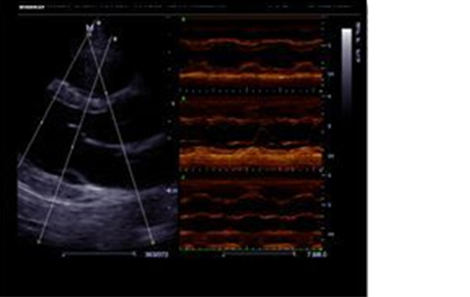

Free Xros M™

Gain precise anatomical observation by freely placing sample lines at any angle. Attain better images through simultaneous display of up to 3 sample lines.

Sample Clinical Images